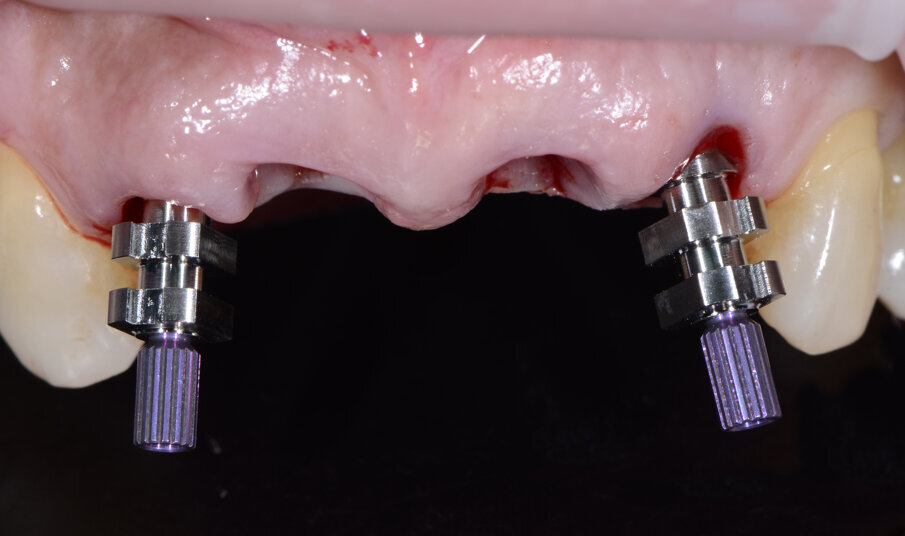

Fig. 32 - Transfert avvitati sugli impianti.

Alloggiamo la dima protesica (Fig. 33), e blocchiamo i transfert con della resina trasparente (tecnica DIL) (Figg. 34, 35). In questo modo possiamo far riposare il paziente in studio dopo appena 35 minuti dall’inizio dell’intervento. La dima protesica, infatti (Fig. 36) con i transfert inseriti viene completata con l’unione degli analoghi ai transfert (Fig. 37). L’insieme così composto viene riadattato sul modello master digitale iniziale (Figg. 38-40) sul quale era stata costruita sia la dima chirurgica che la dima protesica come anche il provvisorio. Gli analoghi vengono bloccati sul modello con resina trasparente (Figg. 41-43). Alloggiamo il provvisorio sul modello master digitale così ottenuto (Figg. 44, 45).

Fig. 34 - Transfert bloccati con resina trasparente.

Fig. 35 - Rimozione dima protesica.